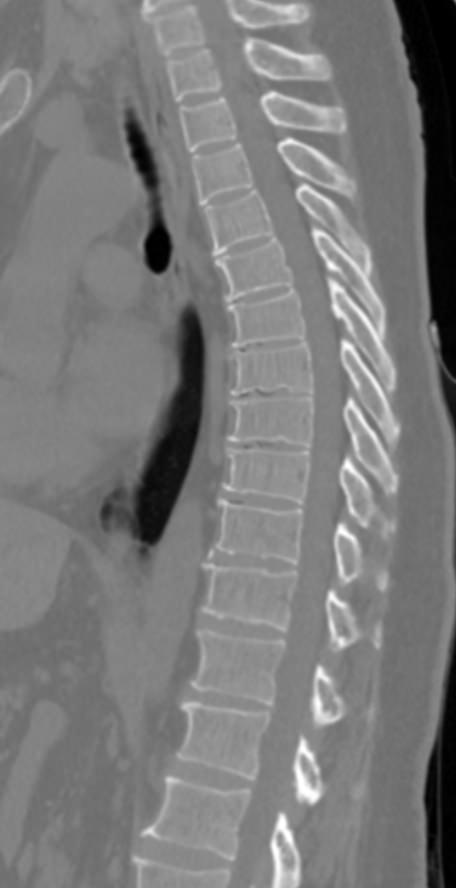

Мультиспиральная компьютерная томография (МСКТ) является современным, высокоинформативным методом диагностики различной патологии позвоночного столба. Благодаря МСКТ можно визуализировать костную структуру позвонков, выявить воспалительные, дегенеративные и опухолевые процессы на исследуемом уровне. В основе метода лежит использование ионизирующего излучения и способность различных тканей по-разному поглощать рентгеновские лучи.

В нашей клинике КТ двух отделов позвоночника проводится на новейших мультиспиральных томографах экспертного уровня TOSHIBA AQUILION (64-срезовый и 128-срезовый). Сканеры производят тончайшие срезы исследуемой зоны толщиной от 0,5 мм и позволяют визуализировать костные структуры позвоночника с высокой детализацией. Увеличенное количество высокочувствительных детекторов аппаратов обеспечивает высокую разрешающую способность и четкость изображений, при этом позволяет выполнить исследование в течение нескольких секунд с минимальной дозой облучения.

Инновационные возможности мультиспиральных томографов, которыми оснащены наши медицинские центры, позволяют создавать 3D-модели позвоночника на рассматриваемом уровне для более точной локализации очага и оценки взаимного расположения органов и тканей.